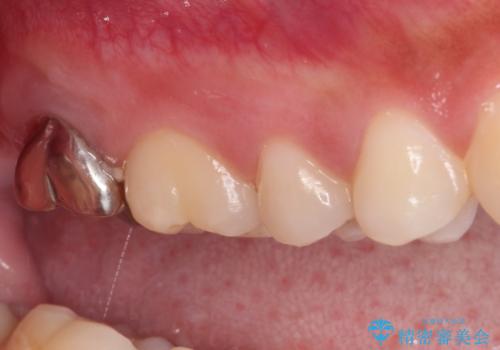

- 奥歯の銀歯に不快感が続くとのことで来院された患者様です。

銀歯の適合が悪く、汚れが溜まりやすくなっており、更には根尖の病変が認められ、咬合時に痛みがありました。

親知らずの存在により、歯肉が歯を覆っているため、親知らずの抜歯により清掃性を改善し、根管治療により痛みを取り除くこととしました。